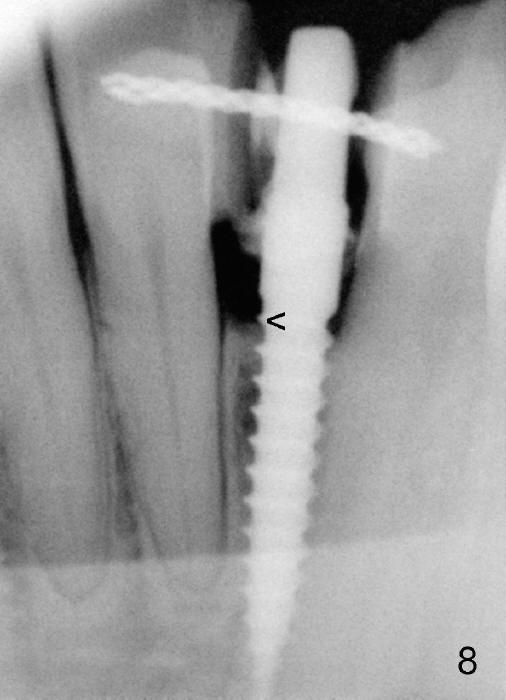

Within the first several days postop, the patient reports mild tenderness from one of the neighboring teeth. Otherwise she is doing fine. Again due to finance, she does not return for restoration for more than 1 year. PA taken 10 months postop shows that there is no abnormality (Fig.7). In fact bone resorption occurs gradually over 2 years 2 months postop, manifested as the 1st thread supracrestal (Fig.8 <). When the 1-piece implant is reprepped for impression 2 years 2 months postop, the micro threads are found apical to the prep margin (Fig.9). The nervous patient has had occasional tooth sensitivity 5 years postop. A narrower implant is more suitable for this case (2.0 or 2.5 mm).